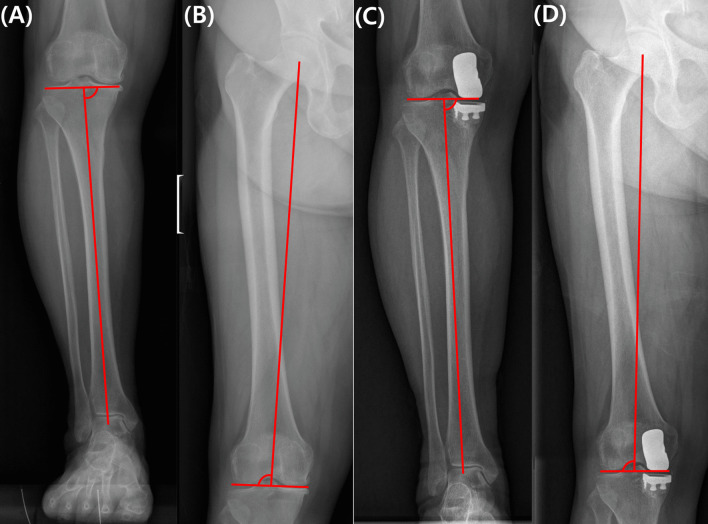

Background: The optimal alignment target for unicompartmental knee arthroplasty (UKA) remains controversial, and literature suggests that its impact on patient-reported outcome measures (PROMs) varies. The purpose of this study was to identify the relationship between changes in the coronal plane alignment of the knee (CPAK) and PROMs in patients who underwent UKA.

Methods: A retrospective analysis of 164 patients who underwent UKA was conducted. The types of CPAK types categorized into unchanged, minor (shift to an adjacent CPAK type, e.g., type I to II or type I to IV), and major changes (transitioning to a nearby diagonal CPAK type or two types across, such as type I to V or type I to III). PROMs were assessed preoperatively and 1 year postoperatively using the Hospital for Special Surgery (HSS) scores, Knee Society (KS) scores, Western Ontario and McMaster Universities Osteoarthritis Index (WOMAC), and Forgotten Joint Scores (FJS). Comparison was performed between patients who experienced and who did not experience any changes in the CPAK.

Results: Patients with preserved native CPAK alignment demonstrated significantly superior 1 year postoperative outcomes, with higher HSS, KS knee, and WOMAC pain scores (p = 0.042, p = 0.009, and p = 0.048, respectively). Meanwhile, the degree of change in CPAK did not significantly influence the PROMs, and patients who experienced minor and major changes in the CPAK showed comparable outcomes.

Conclusion: Preserving the native CPAK in UKA procedures is important for achieving favorable clinical outcomes at 1 year postoperative. The extent of change in the CPAK type exerted a limited impact on PROMs, thus emphasizing the importance of change in alignment itself.